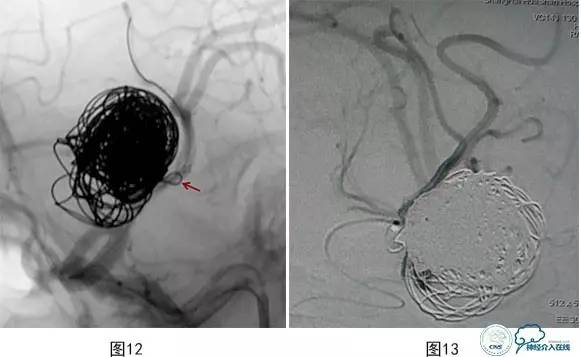

病例3:患者男,27岁。头痛2个月,左大脑中动脉M2段上干起始部靠近分叉部位巨大动脉瘤,下干起始部靠近瘤颈(图10),行支架辅助栓塞治疗,保护下干。术中载瘤动脉闭塞(图11),弹簧圈突入支架内(图12)。

将微导管超选入载瘤动脉注入替罗非班10ml(图13),导引导管内注入替罗非班5ml,血流再通(图14)。术后患者神清,对答切题,伸舌左偏,四肢可遵嘱活动,肌力5级,即刻予以阿司匹林300 mg,氯吡格雷150mg口服。术后20 min,运动性失语,反应迟钝,右侧肢体无力,右上肢肌力0级,右下肢肌力2+,左侧肢体能遵嘱活动,即刻复查颅脑数字减影血管造影(DSA)示:大脑中动脉下干支架内血栓形成,远端血流缓慢(图15)。机械碎栓,部分再通,微导管在上下干开口处2h内分次注入替罗非班共40ml,上干再通,下干分支部分再通,远端可通过软膜吻合显影(图16)。术后患者症状缓解,右侧肢体肌力4+,面瘫消失,部分运动性失语,术后替罗非班静脉微泵维持48h,术后维持收缩压120mmHg以上。术后头颅磁共振弥散加权成像(MR DWI)示左侧大脑中动脉供血区急性梗塞灶(图17)。

图12 弹簧圈突入载瘤动脉支架内-血管急性闭塞

图13将微导管超选入载瘤动脉注入替罗非班10ml

图14 导引导管内注入替罗非班5ml,载瘤动脉血流再通